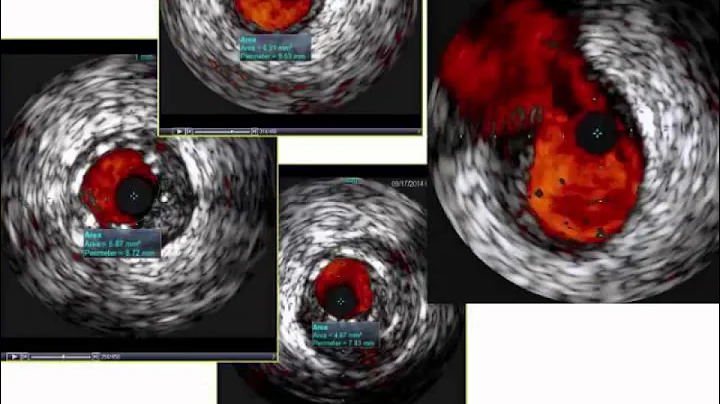

Case and Plan: 78-year-old female presented with NSTEMI. A Cardiac Cath on April 7, 2025 revealed 2 V CAD; 80% proximal ...